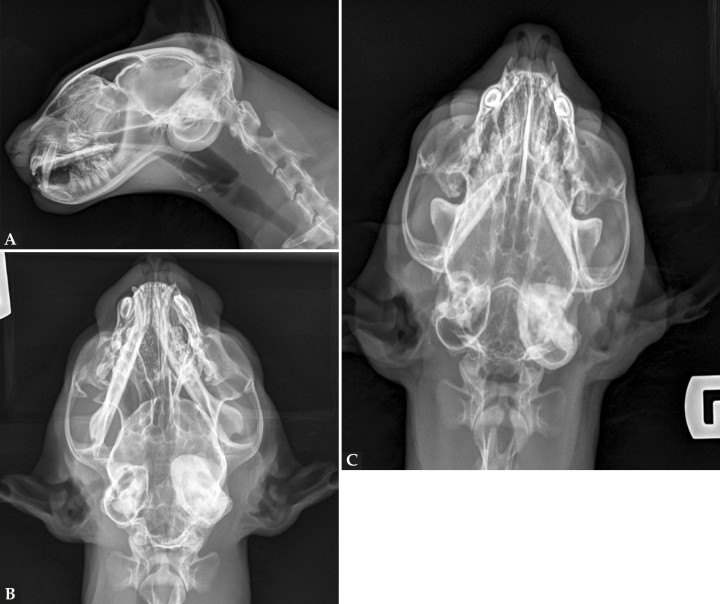

Se realizó un estudio radiográfico de la cabeza del paciente, incluyendo una proyección lateral (Fig. 1A), dorsoventral (Fig. 1B) y rostro 10º ventro-dorsocaudal oblicua (R10ºVCdD) con boca cerrada (Fig. 1C).

Figura 1

Radiografías de la cabeza de un gato maine coon de un año de edad. (A) Proyección lateral. (B) Proyección dorsoventral. (C) Rostro 10º ventro-dorsocaudal oblicua.

Las herramientas de diagnóstico por imagen son necesarias para establecer la extensión y el origen del pólipo. Mediante las radiografías se puede valorar si la nasofaringe se encuentra involucrada y ocupada, o si existe desplazamiento ventral del paladar blando, aumento de opacidad de las BT y/o engrosamiento y grado de esclerosis de sus paredes.2 No obstante, para una adecuada evaluación de las BTs la proyección de elección en la especie felina es la rostro 10º ventro-dorsocaudal oblicua con boca cerrada, al aportar un plano de visualización completo de las BTs.2